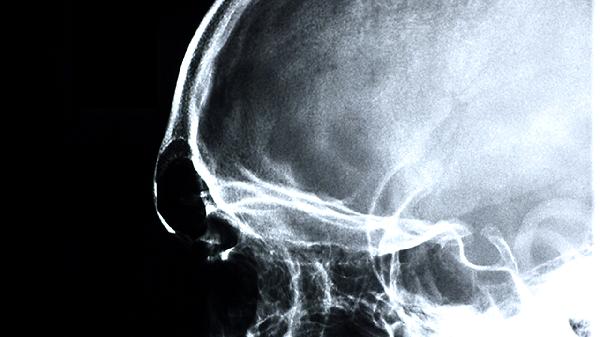

5、脑动脉硬化

对脑供血不足导致的头重脚轻感有一定疗效。患者可能合并记忆力减退、肢体麻木等症状,需配合阿司匹林肠溶片、长春西汀片等改善脑循环药物。日常应控制血脂血糖水平。